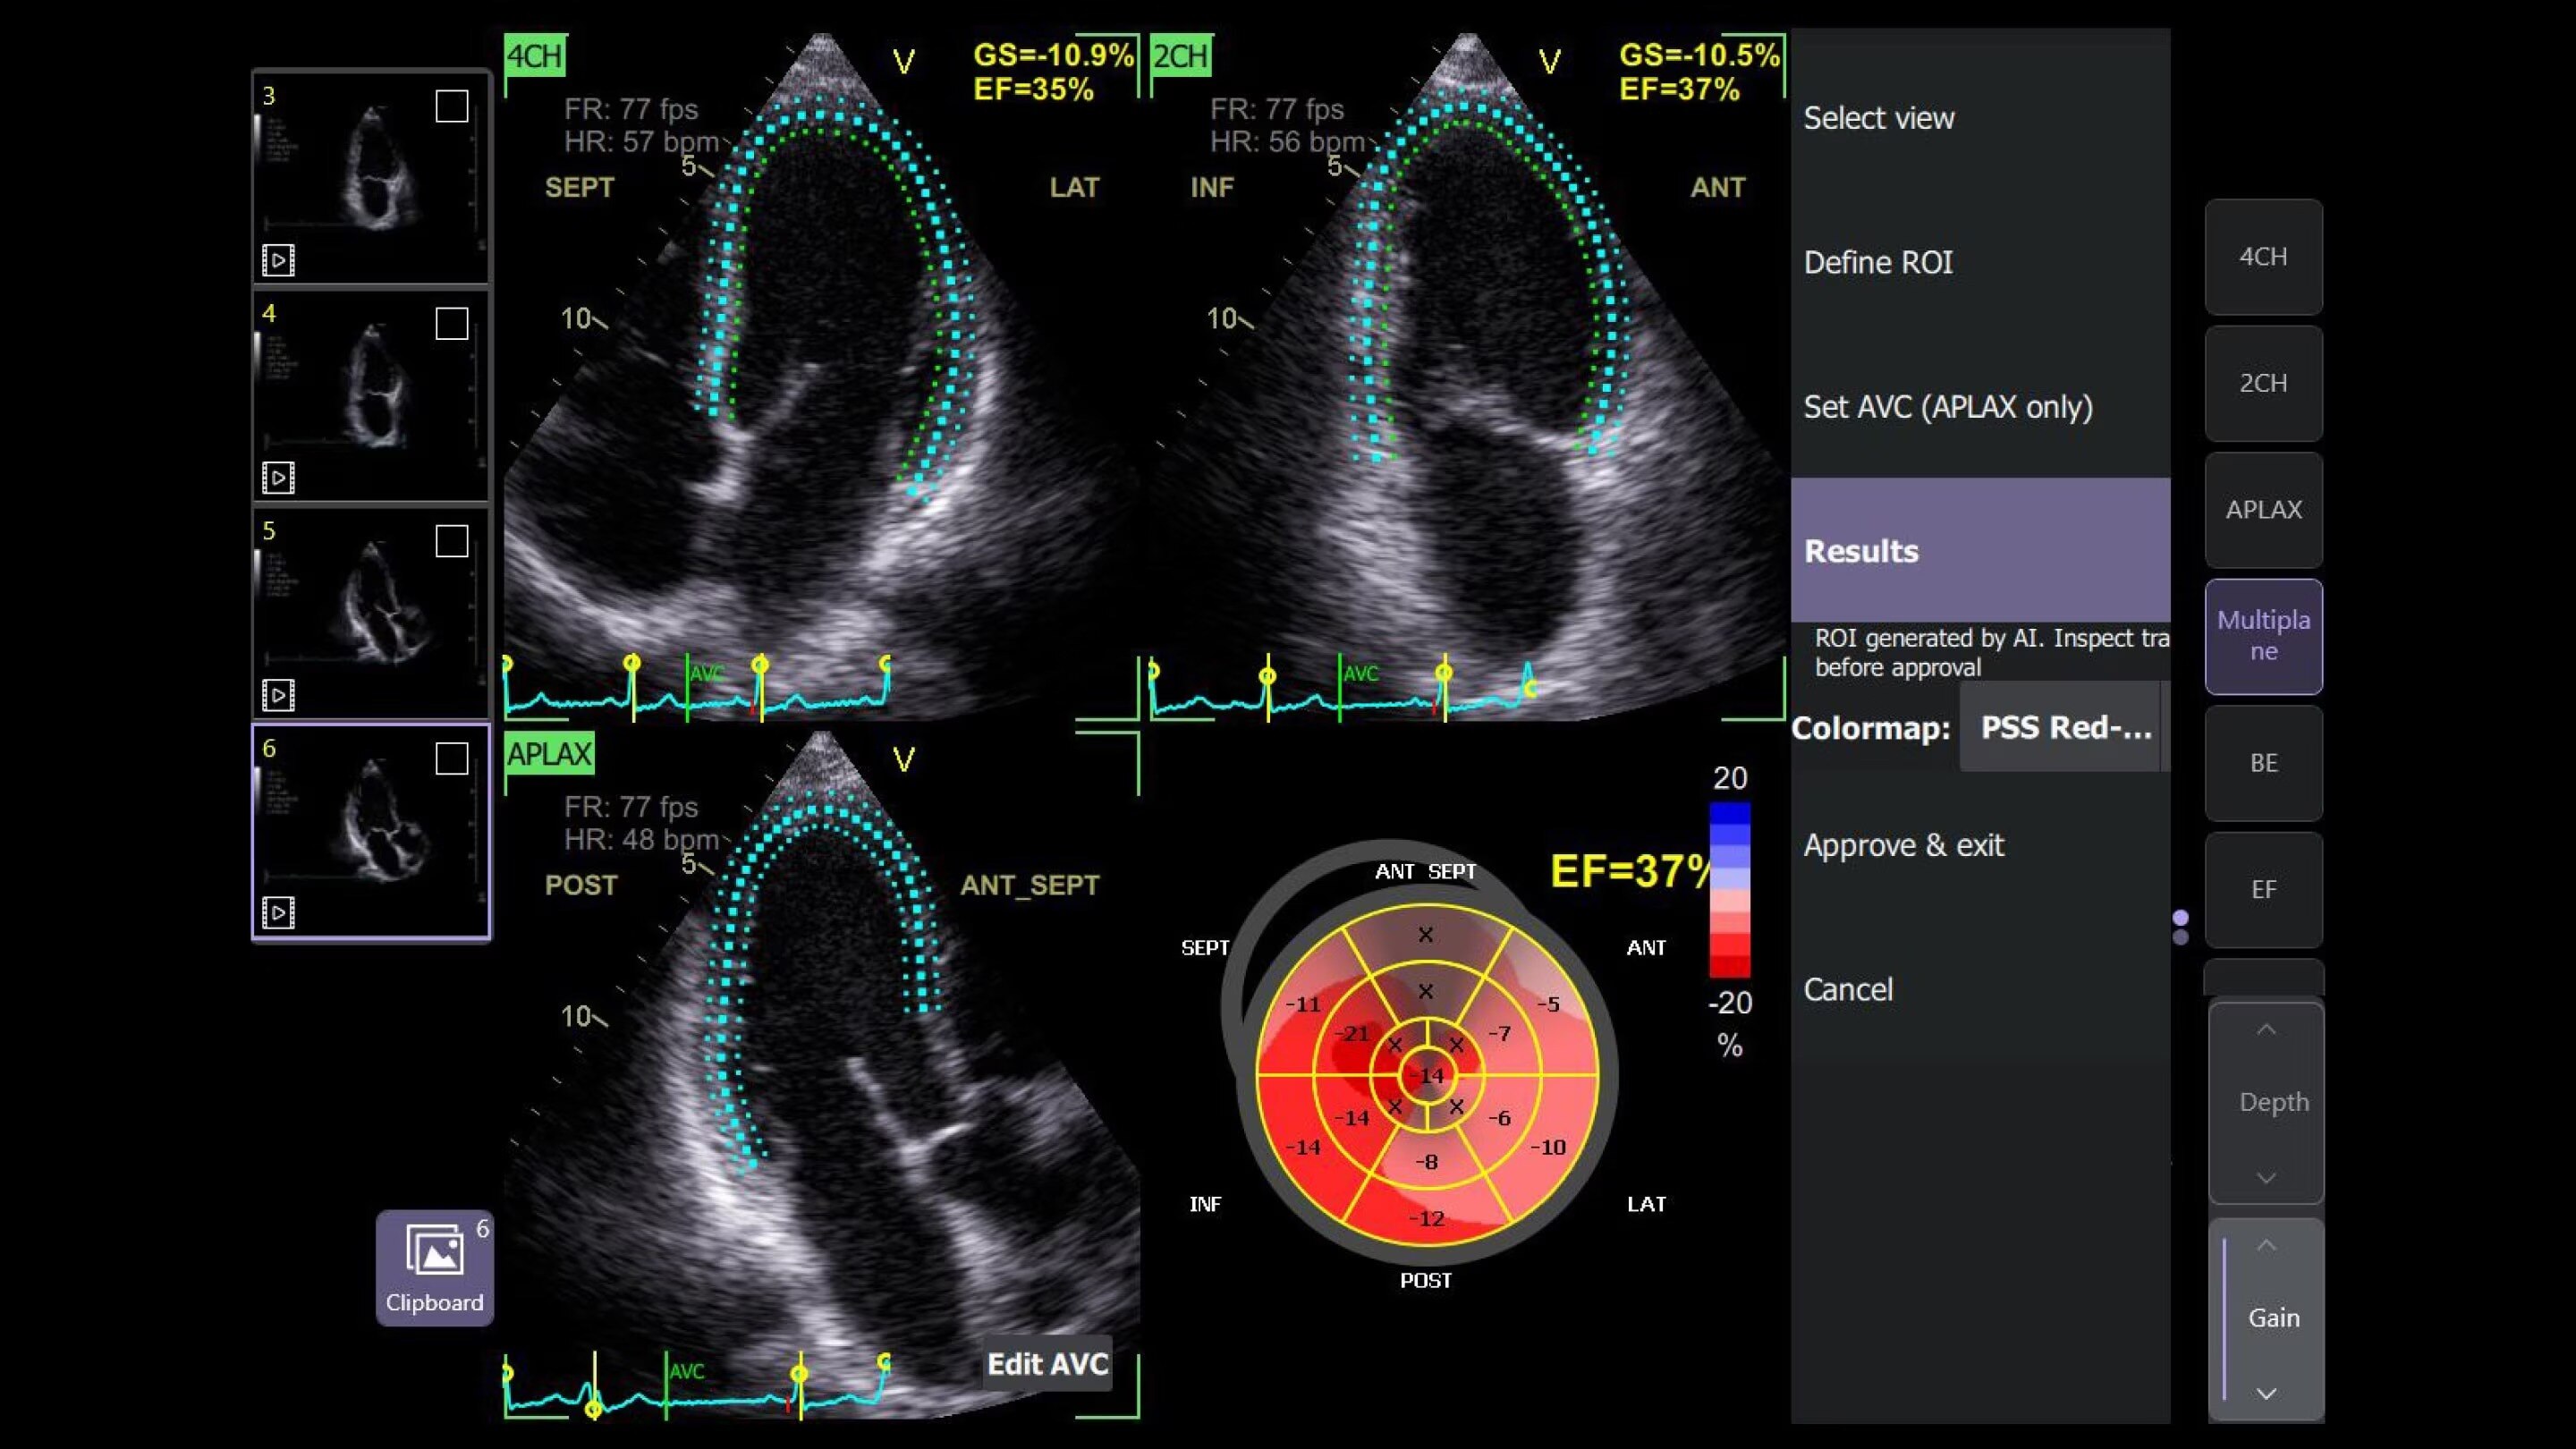

Automated Function Imaging (AFI)

Assess structural heart defects

Quickly and easily assess structural heart defects with objective quantitative analysis of the complete longitudinal myocardial strain of the left ventricle, right ventricle and left atrium throughout the heart cycle. Once you obtain the specific images you need, the AFI measurement tool takes less than three minutes.2